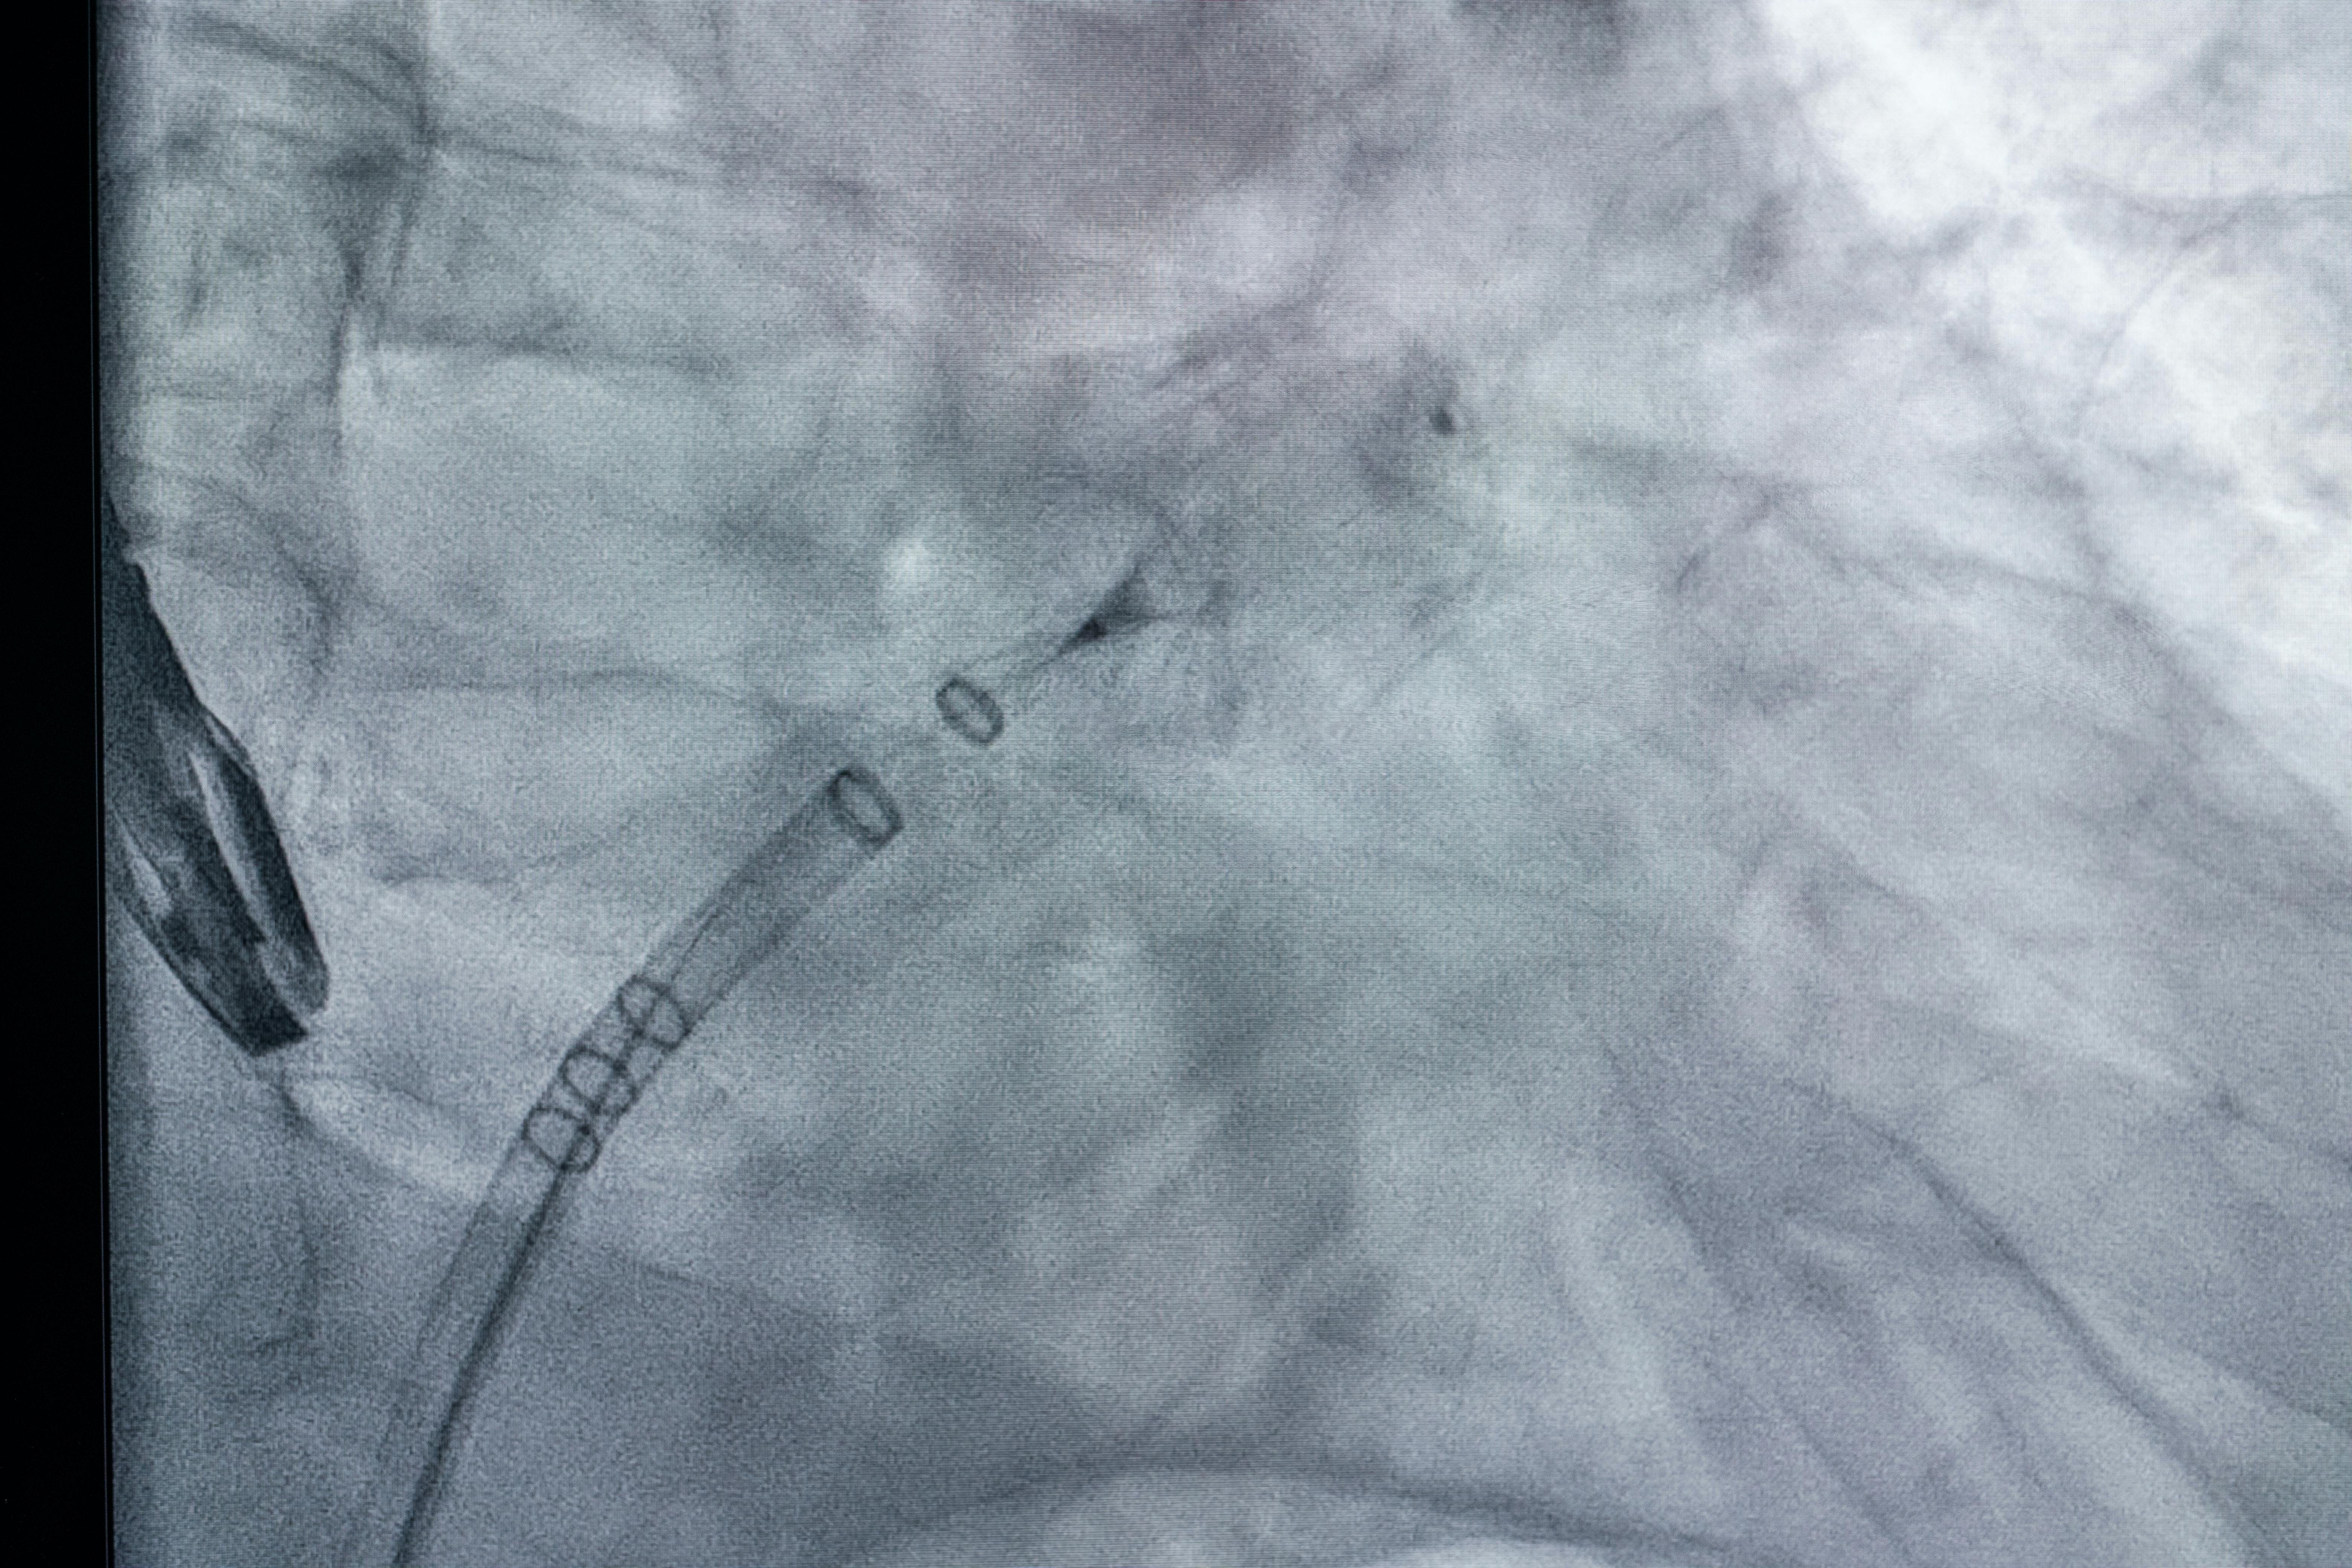

Intervenția a constat în implantarea percutană a unui dispozitiv Watchman FLX de 27 mm, realizată sub anestezie generală și ghidaj ecografic transesofagian, după efectuarea puncției transeptale (acces din atriul drept în atriul stâng).

Rezultatul final a fost optim:

- poziționare corectă a dispozitivului,

- compresie adecvată,

- absența scurgerilor periprotetice (leak-uri),

- pericard liber, fără complicații.